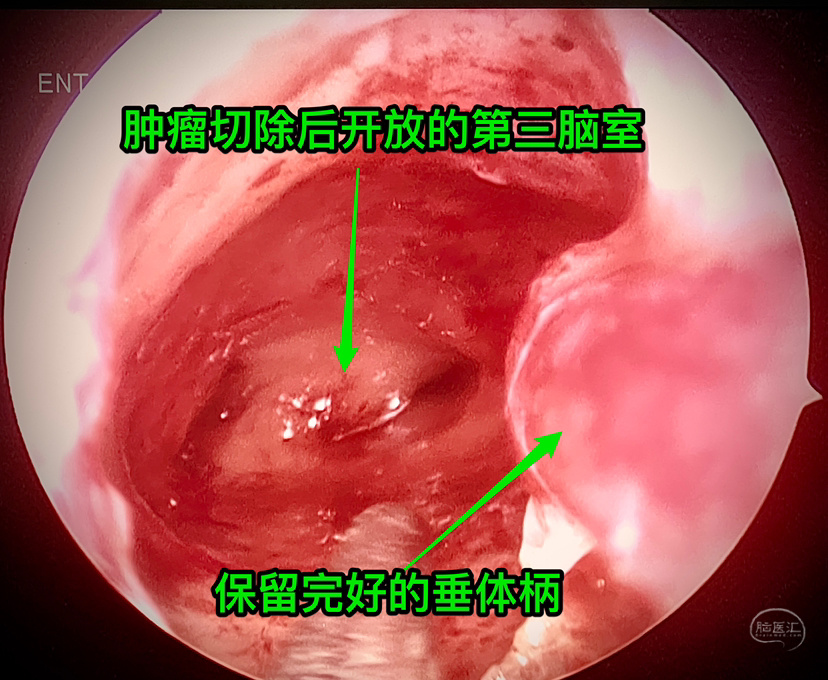

起源点: 术中沿着垂体柄向上切除肿瘤,发现最初肿瘤包绕部分垂体柄,向上探查发现肿瘤起源于垂体柄内,偏一侧,但实际上术中见到肿瘤到了垂体柄内也不一定代表起源就是在这里,如果是生殖细胞肿瘤就有可能是侵入了垂体柄而不是起源于此。“起源点”上方还有一点儿垂体柄,但大多已散开如漏斗结构,问题是:到底是起源于漏斗结节部呢还是下方?不易分辨。